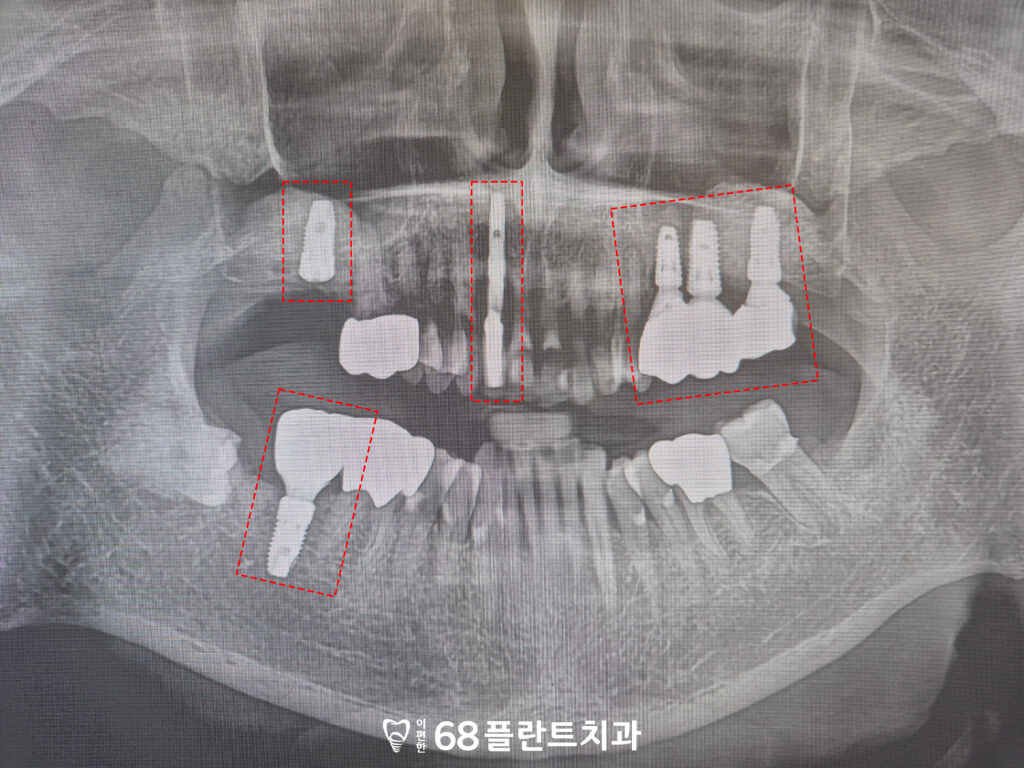

이후 임플란트를 순차적으로 식립하여

상실된 어금니의 기능을 하나씩

회복하는 과정을 진행했습니다.

상악동거상술로 충분한

뼈 높이가 확보된 뒤에는,

무리하지 않고 뼈가 견디는 범위 안에서

단계적으로 임플란트를

식립하는 것이 중요합니다.

이렇게 하면 초기 고정력

확보가 더 안정적이며,

치유 과정에서도 부담이 적어

장기적인 성공률을 높일 수 있습니다.

임플란트가 자리 잡기 시작하면서

상실된 부위들이 자연스럽게 채워지고,

전체적인 교합 균형도 점차 회복되어

환자분이 편안하게 씹을 수 있는

환경을 만들어 갈 수 있었습니다.

그리고 아래 어금니들도

크라운 치료를 시작하였습니다.

신경치료 없이 자연 치아의

신경을 보존한 상태에서

크라운을 진행해

치아를 보호하는 방향으로

설계했습니다.